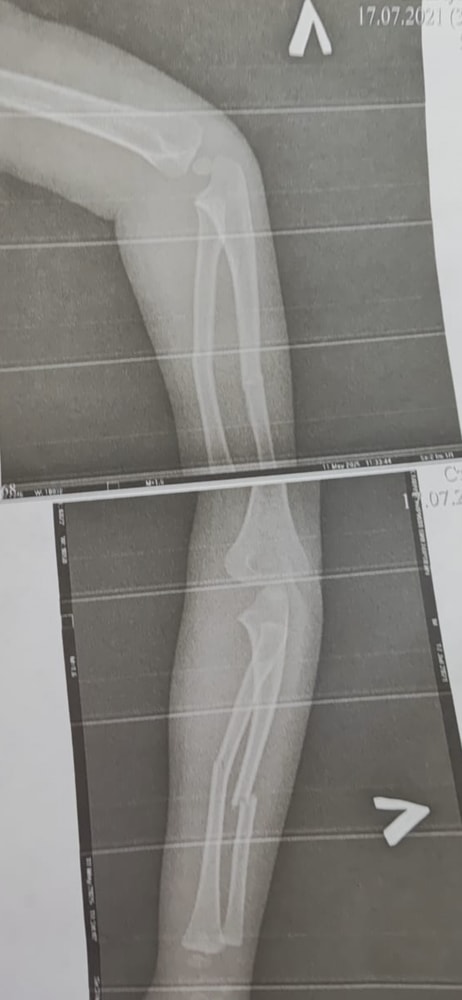

Анализы, УЗИ, РентгенДобрый день . У подруги упал ребёнок , они сейчас в деревне и как поняла перелом со смещением ? Насколько сильно опасно ,можно обойтись без операции ? Им пока просто наложили гипс,она тоже не знает как лучше в этой ситуации

Когда со смещением обычно делают операцию, тем более ,судя по рентгену смещение достаточное. Пусть из деревни в город едут, начнется сращение,потом опять ломать придется, или уже оставить как есть,а это чревато в дальнейшем.. кости растут, участок сращения тонкий, повышается вероятность повторных переломов.. вся жизни на ногах впереди